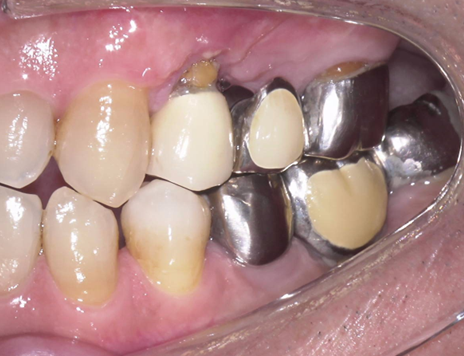

①歯根破折により右上小臼歯が動揺し、歯肉が腫れてしまい、周囲の歯槽骨が吸収していてインプラント埋入

が出来ないと他院で診断され、当院にインプラント治療を希望されました。

予定通りジルコニアクラウンにて、インプラント修復が行えました。